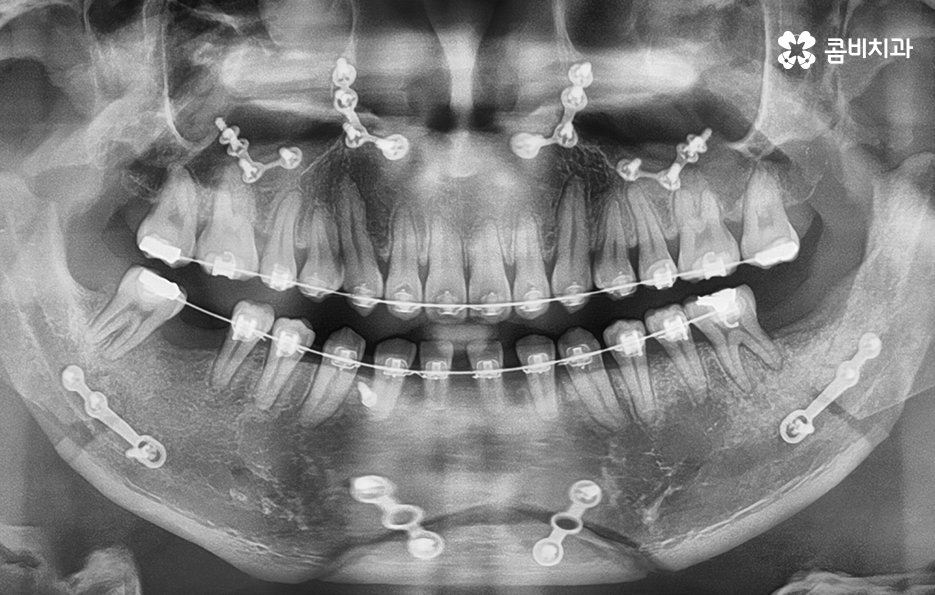

위 환자분의 경우 충치로 인해 오른쪽 아래 제1대구치와

왼쪽아래 제2대구치가 상실된 상태였으며, 치아교정만으로는

치료가 불가능한 케이스였기 때문에 비발치 교정으로

진행하면서 외과수술이 병행된 케이스라고 할 수 있어요

클리피씨교정을 통해서 약 1년 6개월간

치료가 진행이 되었고, 수술과 병행이되며, 치료 마무리 단계에서

임플란트 수술까지 진행이 된 사례라고 볼 수 있는데요.

위 환자분의 경우 수술과 병행되어 비발치 교정으로 진행되었기 때문에

약 1년 6개월 정도의 기간이 소요되었으며

교정 후 교합이 정상적으로 맞물리는 것을 확인할 수 있어요.